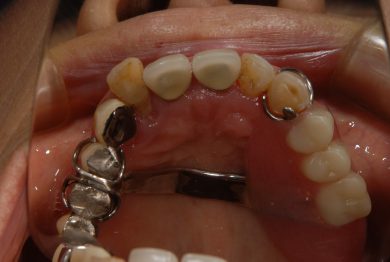

テンポラリーインプラントを用いながら、歯が無い日をほぼなくし、患者さんが困らないように、仮歯を入れて少しは咬める環境を作りました。

この方は術後10カ月で治療が完了しました。歯周病予防処置とあわせて計18回のご来院です。インプラント治療に関しては、10回です。

インプラント6本 サイナスリフト2ヵ所 オールオン6 仮歯 総費用約350万